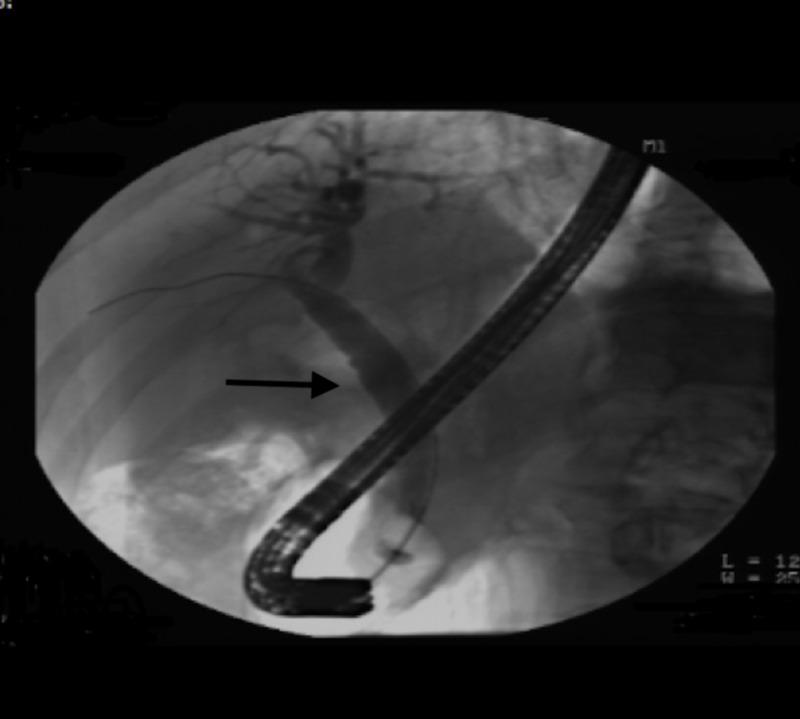

Neuroendocrine tumors (NETs) of gastrointestinal tract are rare entities. Their presence as synchronous lesions with adenocarcinoma has rarely been described in the literature. Cases of synchronous lesions of adenocarcinoma with neuroendocrine component have been described in the colon in the past. However, synchronous presence in the ampulla of Vater is quite uncommon. In the duodenum, NETs constitute 5.7 to 7.9% of the neuroendocrine neoplasms of the gastroenteropancreatic tract. We present a case of 65-year-old male who presented with abdominal symptoms and weight loss, was found to have adenocarcinoma of the ampulla of Vater on biopsy via endoscopic retrograde cholangiopancreatography (ERCP), for which he underwent Whipple's surgery and was found to have neuroendocrine component along with adenocarcinoma postoperatively on histology.

胃肠道神经内分泌肿瘤(NETs)是罕见的疾病。它们作为与腺癌同步出现的病变在文献中很少被描述。过去曾有过结肠中腺癌与神经内分泌成分同步病变的病例报道。然而,在 Vater 壶腹出现同步病变相当罕见。在十二指肠,NETs 占胃肠胰道神经内分泌肿瘤的 5.7%至 7.9%。我们报告一例 65 岁男性,因出现腹部症状和体重减轻就诊,经内镜逆行胰胆管造影术(ERCP)活检发现患有 Vater 壶腹腺癌,为此他接受了 Whipple 手术,术后组织学检查发现除腺癌外还存在神经内分泌成分。